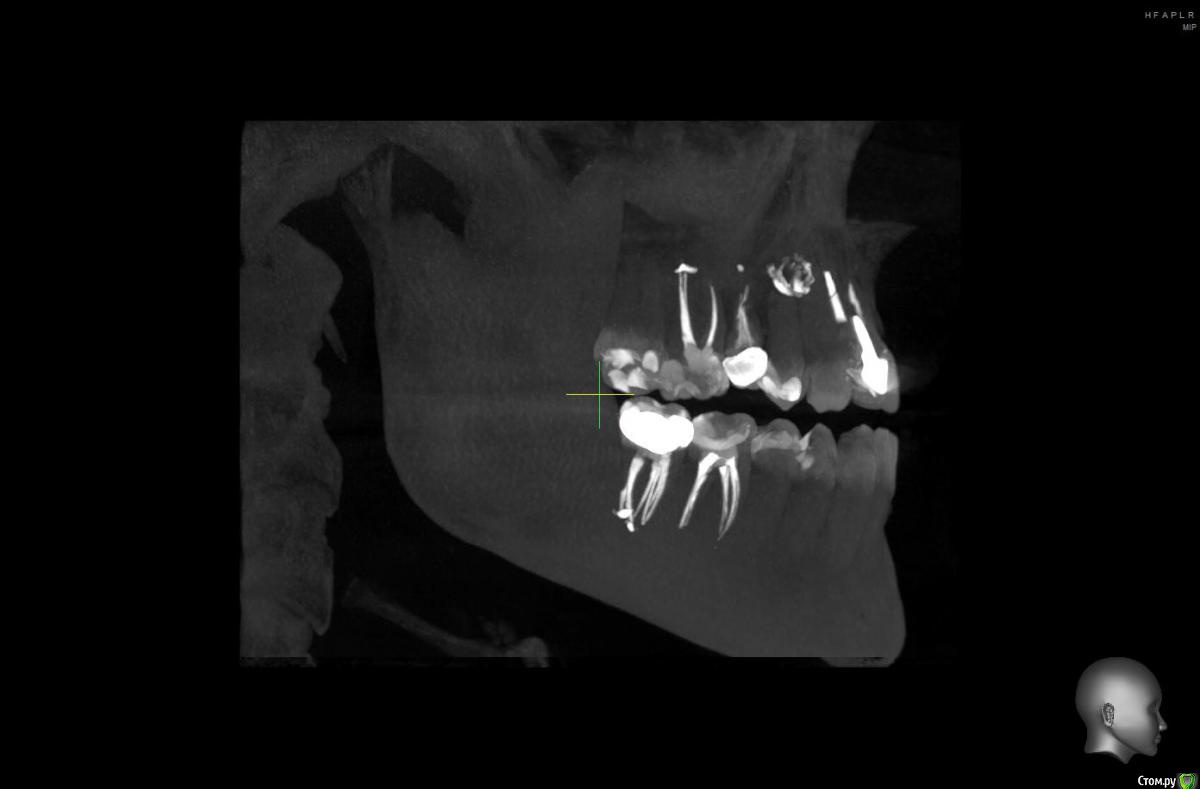

10 лет назад на передних зубах были установлены металлокерам.коронки, на одном из зубов-металлический штифт. (Фото прилагаю)

В 2019 году я решилась поменять коронки, в одном из зубов нашли кисту, долго лечили, вывели лекарство за корень, потом другой врач через микроскоп все пролечил и запломбировал. Решили не делать резекцию, пока не беспокоит.

Ссылку на КТ прилагаю, не знаю откроется или нет.

https://drive.google.com/open?id=1fp042ssCNfvp3B19SGM4TykOPuuaK5gu